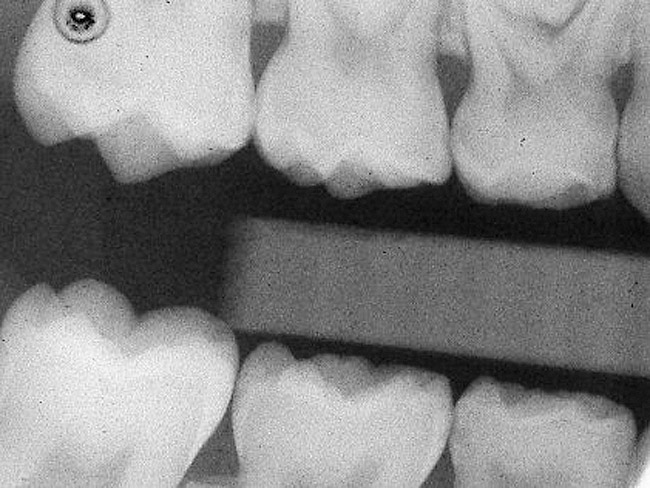

Figure 2  Preoperative radiograph showing mesial incipient lesion on tooth A.

Figure 2